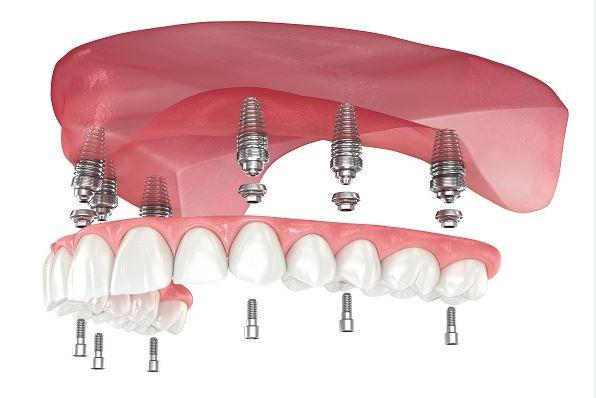

Another option involves placing four to six implants, depending on your jaw’s size and shape, into your lower jaw. After healing is complete, the implants are connected with a custom-made support bar. Your denture will be made with special internal retention clips that attach onto the support bar, enabling the denture to snap firmly into place. This is called an “overdenture.” The advantage of this option is that it is much more stable than the first option and allows very little denture movement. Your denture is still removable for easy cleaning and maintenance.

A third option involves placing five or more implants in your jaw and attaching a permanent denture. Your denture is held in place by screws or clasps that secure it to the support posts or bar. It doesn't touch the gum tissue, which allows you to clean under the denture without removing it. This denture will replace all your missing lower teeth and will not be removed except at maintenance visits. Although cleaning under your denture without removing it is more time consuming and requires more dexterity, many patients who want a permanent denture prefer this option.

The final option is to replace each tooth individually so that they appear to naturally emerge from your gum tissue, closely mimicking the look of your natural teeth. Typically, this comprehensive approach requires eight or more implants, with each implant receiving its own abutment or support post and a custom-made crown for the missing tooth. In some cases, the crowns may be connected to facilitate sinus grafting, which helps restore bone height, strength, and support. This method is generally the most costly option due to the extensive implant work and individual tooth fabrication involved. Additionally, the feasibility of this option may be limited by the current size and shape of your jawbone.